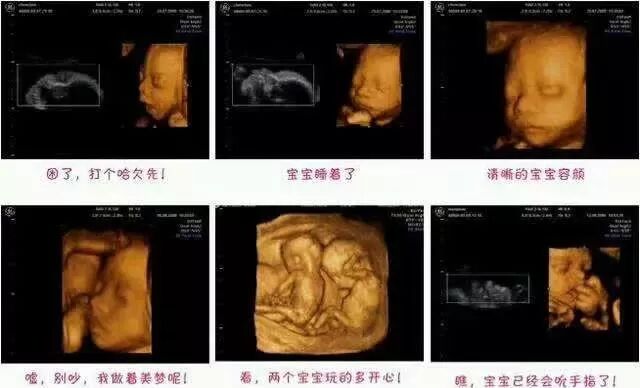

四维彩超的全称为四维彩色超声诊断仪,是目前世界上最先进的彩色超声设备。四维彩超的诊断资料有利于医生检测出各种异常,对于胎儿的成长发育做出准确的判断。

由于孕妇有个体差异,什么时候去做四维彩超要因人而异,一般来说,怀孕22-26周是照四维彩超的最佳时间。因为这一阶段胎宝宝结构已经形成;胎宝宝的大小及羊水适中;胎宝宝骨骼回声影响比较小,图像清晰,所以,这个时期是进行胎儿畸形检测最为理想的时期,可排除大部分的畸形。